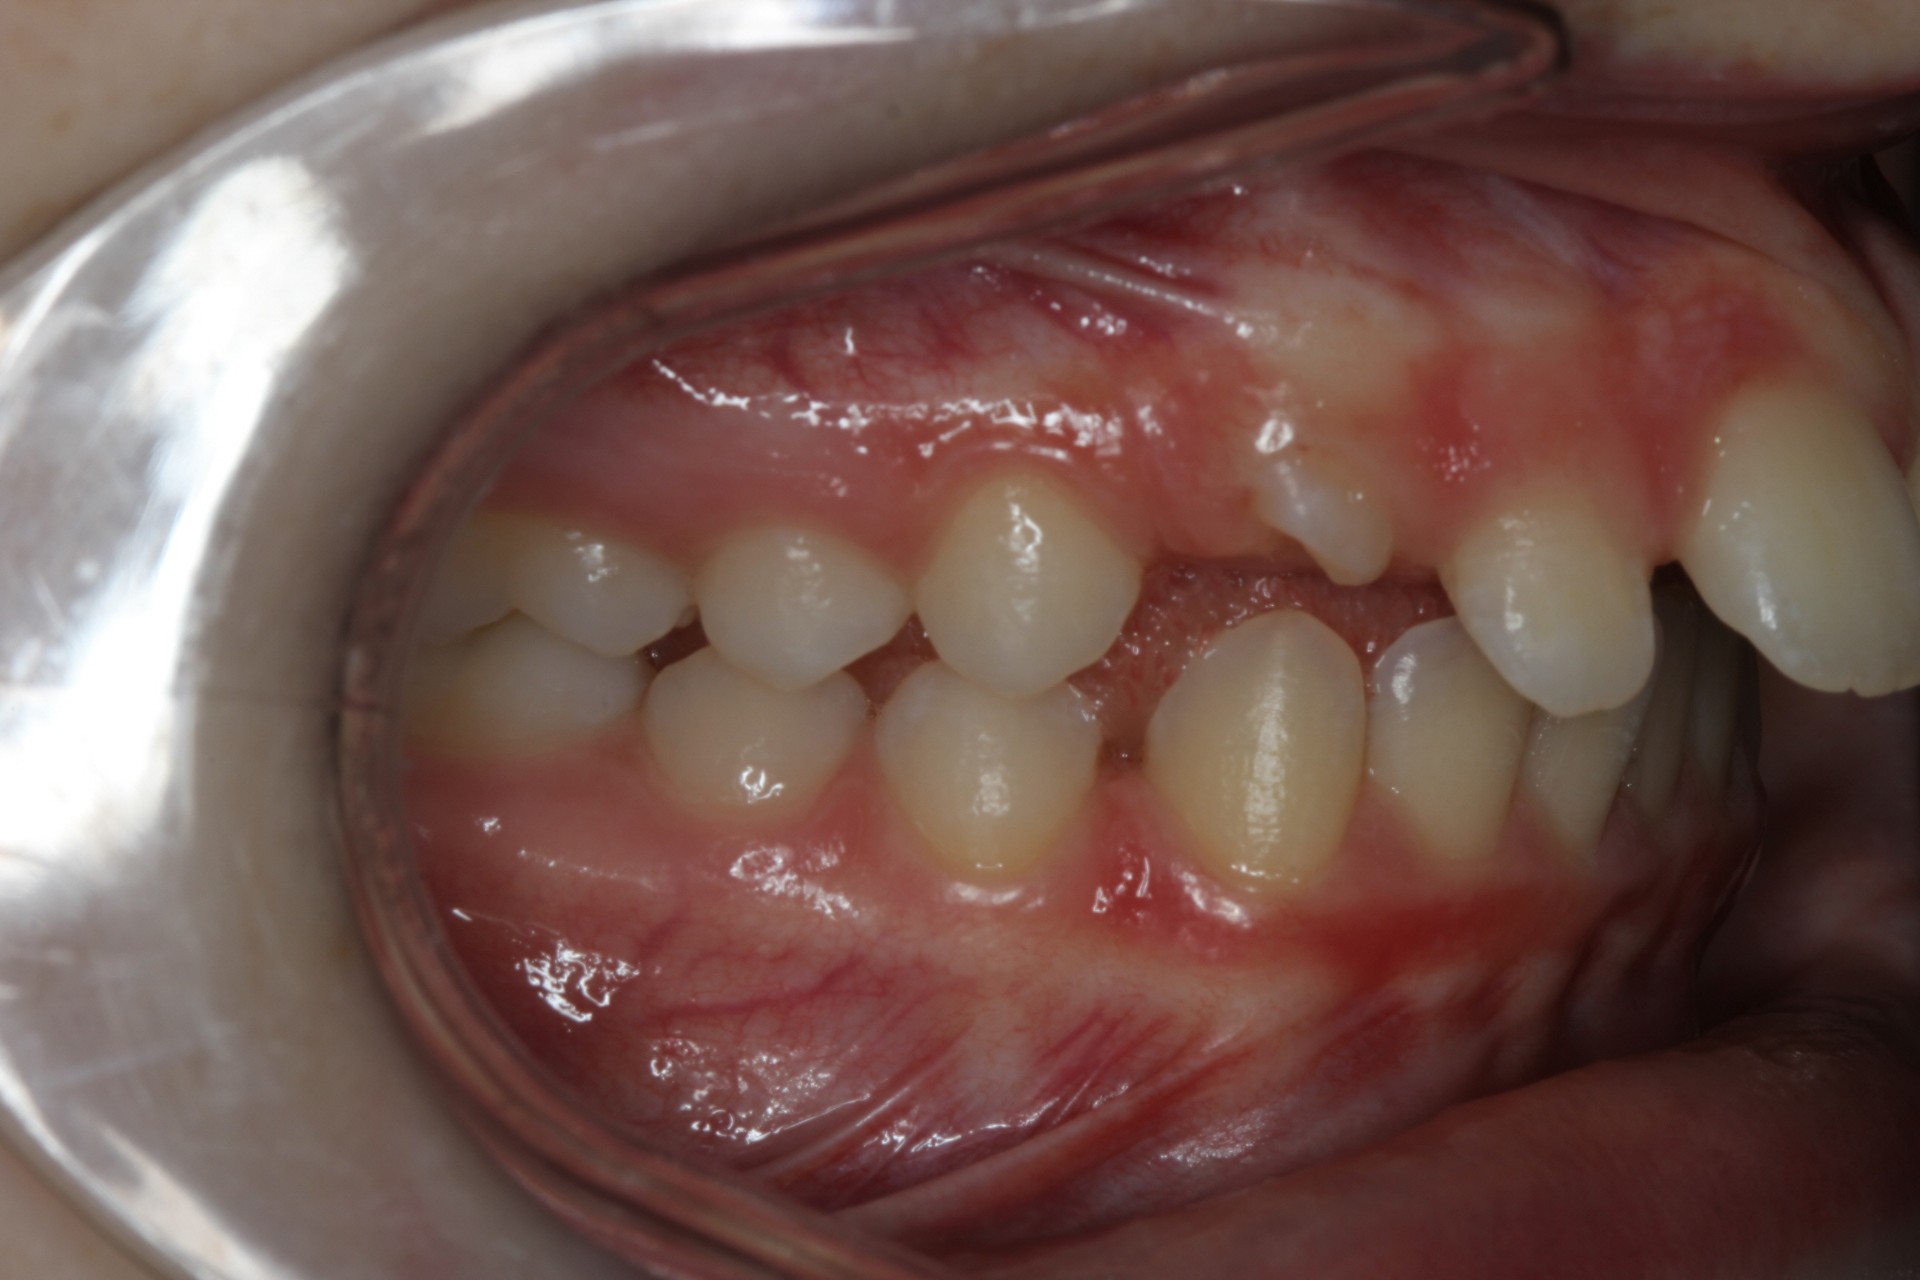

Protruding front teeth – Child case

Protruding front teeth and spacing – Child case

Protruding front teeth with midline diastema – Child case